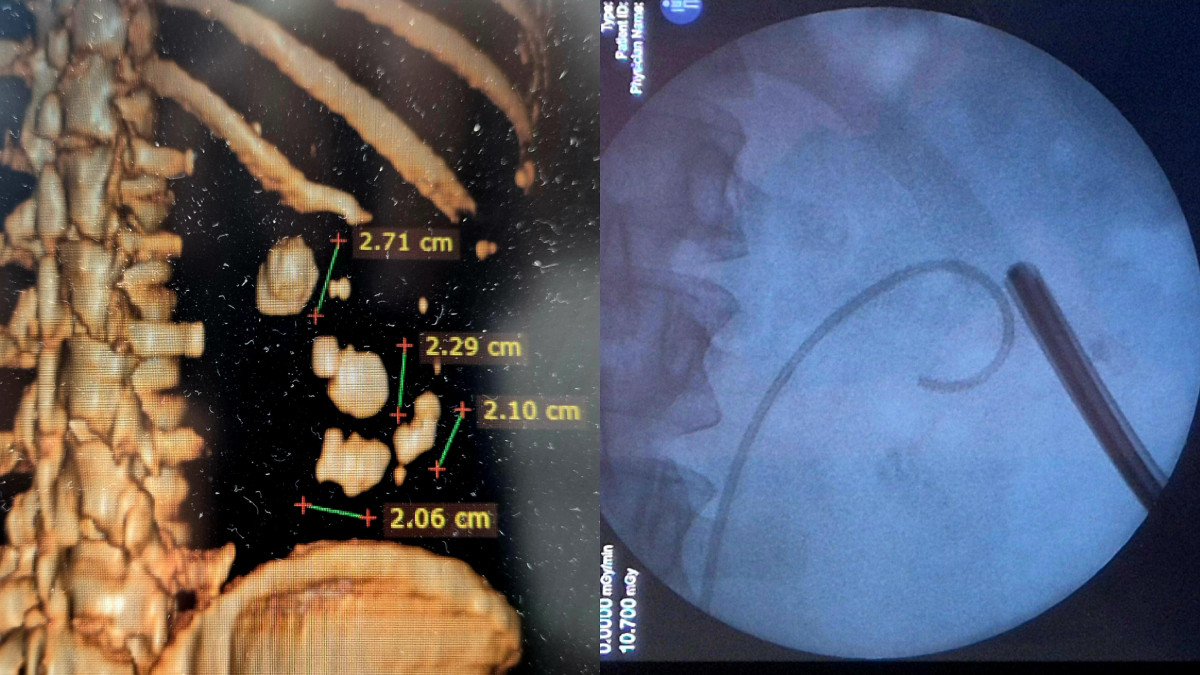

Д-р Петър Вътов е специалист уролог във Варна и Бургас с 10 години медицински опит, с интереси в областта на онкоурологията, бъбречно-каменна болест и симптоми на долните пикочни пътища. Предлага на пациентите си конвенционални и съвременни минимално инвазивни методи на лечение на заболявания на горни и долни пикочни пътища.

• Курс по лечение на БКБ чрез PCNL - Prof. Liatsikos, Patras - 2023г.

• Курс по лечение на БКБ чрез RIRS и PCNL - Проф. Илия Салтиров, ВМА - София- 2023 и 2024г.